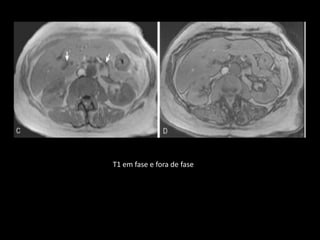

T1 em fase e fora de fase

T2: ducto pancreático

ANATOMIA RM NORMAL

GRE T1 em fase: hiperintenso devido ao conteúdo

adiposo;

Fora de fase: queda do sinal;

T1 com contraste: realce intenso e eliminação

rápida;

O DPP é visualizado como uma estrutura de sinal

forte em T2 e na CPRM.

Os ramos laterais não são vistos à RM ou CPRM;

Uso de secretina